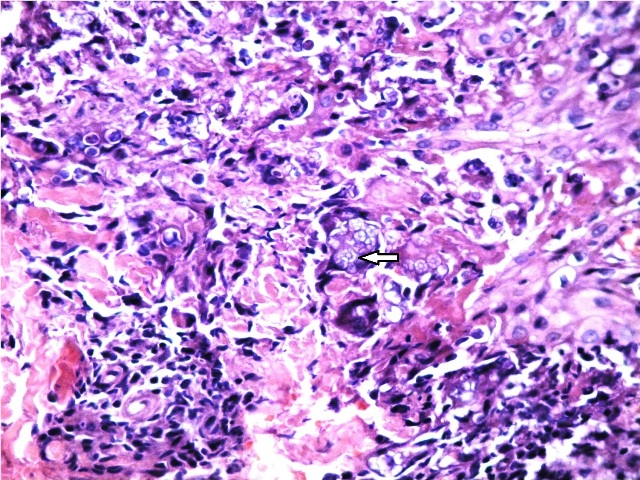

Fig 4: Basophilic spherules of prototheca are seen (40X).